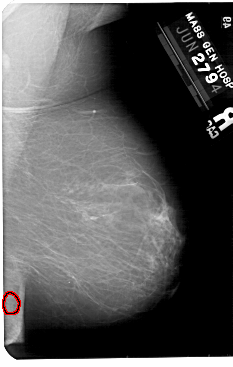

A_1561_1.RIGHT_MLO

RIGHT_CC LINES 5476 PIXELS_PER_LINE 3391 BITS_PER_PIXEL 12 RESOLUTION 43.5 OVERLAY

FILE: A_1561_1.RIGHT_MLO.OVERLAY

TOTAL_ABNORMALITIES 1

ABNORMALITY 1

LESION_TYPE CALCIFICATION TYPE PLEOMORPHIC DISTRIBUTION CLUSTERED

ASSESSMENT 3

SUBTLETY 3

PATHOLOGY BENIGN

TOTAL_OUTLINES 1

BOUNDARY